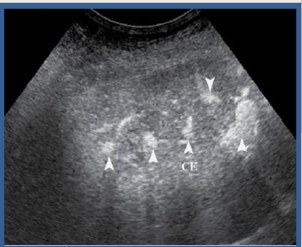

what lesion is this on CEU?

FNH